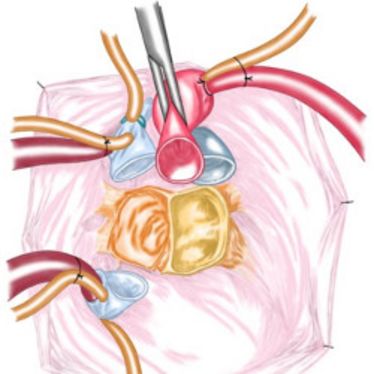

"7. Münsteraner Frühjahrssymposium für Orthopädie und Orthopädische Chirurgie" (Fortbildung)

"7. Münsteraner Frühjahrssymposium für Orthopädie und Orthopädische Chirurgie" (Fortbildung)

31. Jahreskongress der Deutschen Gesellschaft für Gefäßchirurgie und Gefäßmedizin (Fortbildung)

31. Jahreskongress der Deutschen Gesellschaft für Gefäßchirurgie und Gefäßmedizin (Fortbildung)